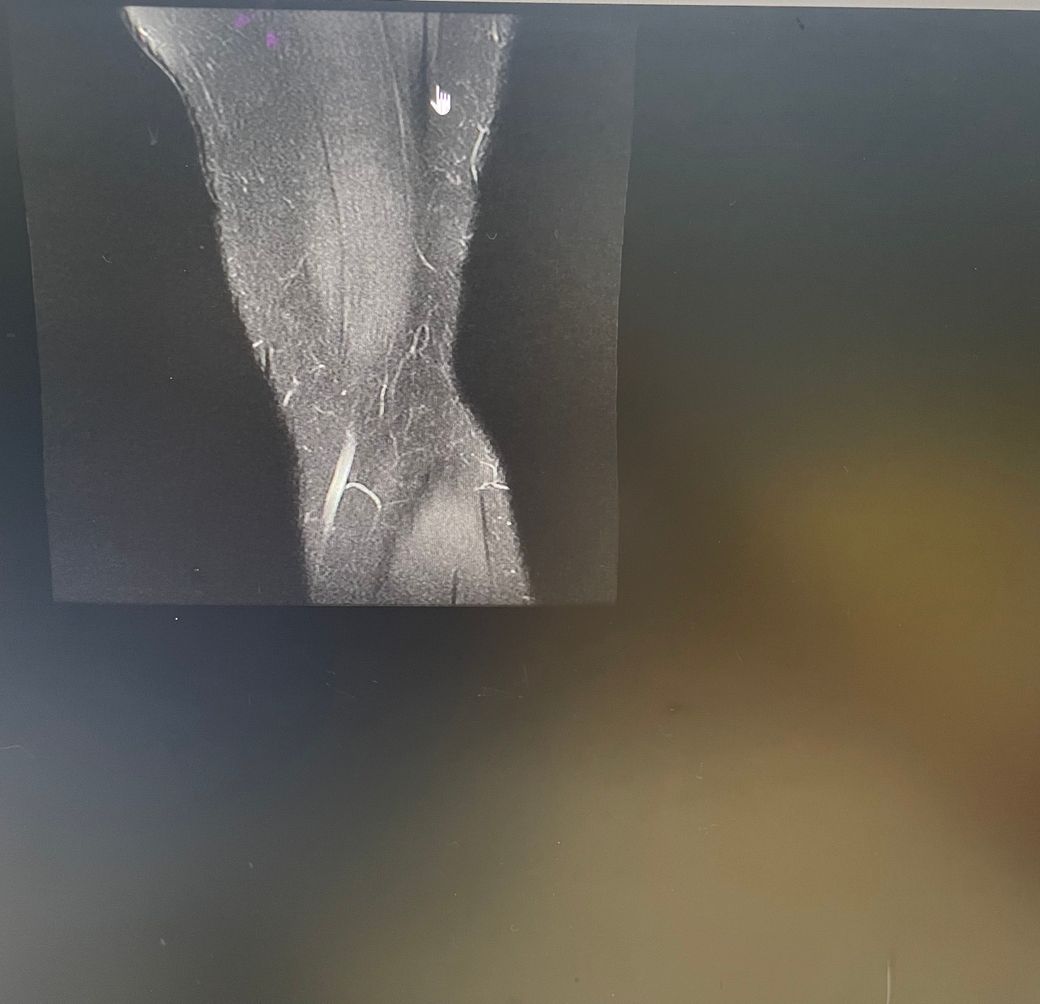

무릎 왼쪽 mri 사진 판독 부탁드리겠습니다.

안녕하세요 3달전쯤에 무릎을 다쳐서 약 한달전에 mri를 찍었습니다.

ACL 즉 전방 십자 인대에 불규칙한 소견은 있으나 Tear 즉 십자 인대가 파열되었다는

소견은 관찰되지 않는 상태이며 연골에 퇴행성 변화는 있는 것으로 보이나 이 역시 R/O

으로 확실하지 않음을 의미합니다. 결과적으로 십자 인대의 파열이 명확하지 않는 상태로